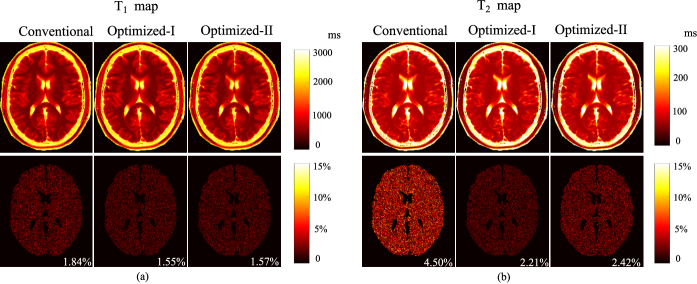

Refer to caption

Figure 10: Bias-variance analysis of the reconstructed parameter maps from the highly-undersampled MR fingerprinting experiments (N=400𝑁400N=400 and SNR=33dBSNR33dB\mathrm{SNR}=33~{}\mathrm{dB}), using the acquisition parameters from the conventional scheme, Optimized-I, and Optimized-II. (a) Normalized bias, standard deviation, and root-mean-square error for (a) T1subscript𝑇1T_{1} maps and (b) T2subscript𝑇2T_{2} maps. The regions associated with the background, skull, scalp, and CSF were set to be zero.

III-A5 Evaluation of highly-undersampled experiments

We repeated the same evaluations but applied to the highly-undersampled case. Note that this more closely matches the way that MR fingerprinting is applied in practice. Fig. 9 shows the reconstructed T1subscript𝑇1T_{1} and T2subscript𝑇2T_{2} maps from the highly-undersampled experiments at N=400𝑁400N=400 and SNR=33SNR33\mathrm{SNR}=33 dB, using the conventional scheme, and the two optimized schemes. As can be seen, Optimized-I improves the accuracy of the T2subscript𝑇2T_{2} map over the conventional scheme, but at the expense of degrading the accuracy of the T1subscript𝑇1T_{1} map. In contrast, Optimized-II provides better accuracy for both T1subscript𝑇1T_{1} and T2subscript𝑇2T_{2} maps, which is highly desirable. Note that the ML reconstruction involves solving a nonlinear and nonconvex optimization problem, for which a good initialization is often required. By enforcing the additional constraint on the flip angle variations, Optimized-II results in much smoother magnetization evolutions (as shown in Fig. 3). With the highly-undersampled data, this often leads to better pattern matching results for the conventional reconstruction, which in turn provides an improved initialization for the ML reconstruction.

Fig. 10 shows the normalized bias, standard deviation, and root-mean-square error maps for the reconstructed T1subscript𝑇1T_{1} and T2subscript𝑇2T_{2} maps from the MC simulations (with 100 trials). Clearly, Optimized-II reduces the normalized standard deviation and root-mean-square error for both T1subscript𝑇1T_{1} and T2subscript𝑇2T_{2} maps, compared to the conventional scheme. Moreover, with smooth magnetization evolutions, Optimized-II reduces the bias compared to Optimized-I. This further illustrates the merit of introducing the constraint on the flip angle variations for the highly-undersampled experiments.